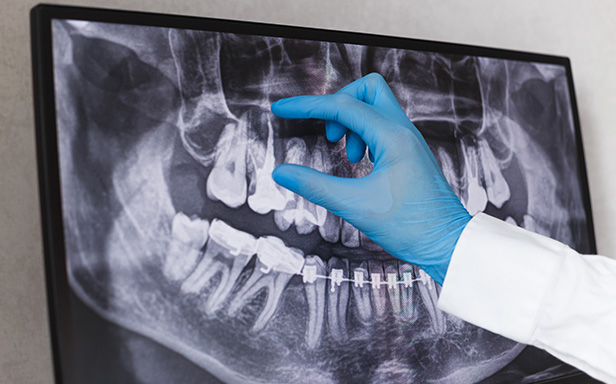

| 歯科用CTによる三次元診断 | 拡大ルーペの使用 |

| 一般的なレントゲン(二次元)では見えない、歯根の複雑な構造や病巣の位置を立体的に正確に把握し、治療の見落としを防ぎます。 | 肉眼では困難な根管内の細部を約8倍に拡大して確認し、処置の精度を高めます。 |

| 歯科用CTによる三次元診断 |

| 一般的なレントゲン(二次元)では見えない、歯根の複雑な構造や病巣の位置を立体的に正確に把握し、治療の見落としを防ぎます。 |